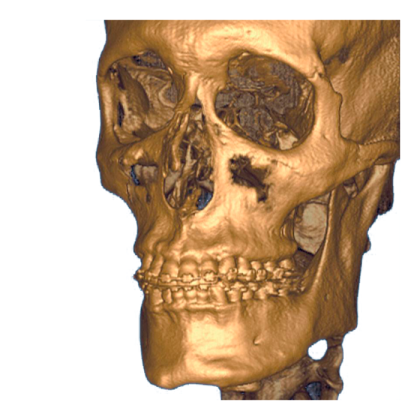

i-CAT 3D eXam представляет собой высокотехнологичное рентгенографическое устройство, сочетающее функции панорамного и томографического сканирования для детальной визуализации стоматологических структур. Аппарат осуществляет как панорамные, так и 3D снимки, обеспечивая точную диагностику и моделирование челюстей.

Прибор оснащен передовым датчиком из аморфного кремния, который предоставляет точное получение данных за 8,9 секунд сканирования, а время реконструкции 3D-модели составляет около 20 секунд. Базовый режим сканирования охватывает область размером 8,5x8,5 см, что позволяет детально анализировать зубные ряды и челюсти. Для более широкого охвата доступны расширенные режимы с полем до 23x17 см.

- Программное обеспечение для диагностики i-CatVision / eXamVision и 3DVR